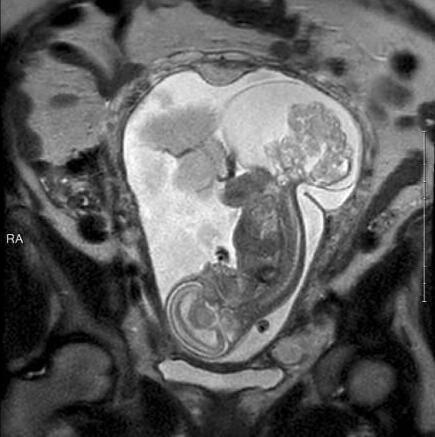

今年6月,琳莉23周零5天的时候,玛格丽特在德克萨斯儿童医院接受了手术,这个时候的肿瘤都快比琳莉大了。手术共进行了5个小时。“摘除肿瘤时我们做得很快,只花了20分钟。最花时间的是打开子宫。我们不想让妈妈的健康受到影响,所以进行得很仔细。”

由于肿瘤已经很大,要取出来的话还是需要切口,所以摘除肿瘤时胎儿完全离开了玛格丽特的子宫,暴露在空气中。“所有的羊水也出来了,非常神奇。”卡斯医生说。手术中,琳莉的心脏仅保持低频跳动,都快停止了。卡斯邀请了心脏专家协助手术。心脏专家保持琳莉的心脏处于可接受的状态,以保证手术的顺利进行。

医生们摘除了大部分肿瘤。手术结束后,医生把琳莉放回了妈妈的子宫内,然后缝合了子宫。“我们打开子宫再缝上它,这个尝试居然成功了,这简直就是个奇迹。”卡斯医生激动地说。手术结束后,玛格丽特需要一直躺在床上休息,直到妊娠期结束。接下来的12周里,玛格丽特一边忍受疼痛,一边期待琳莉的出生。